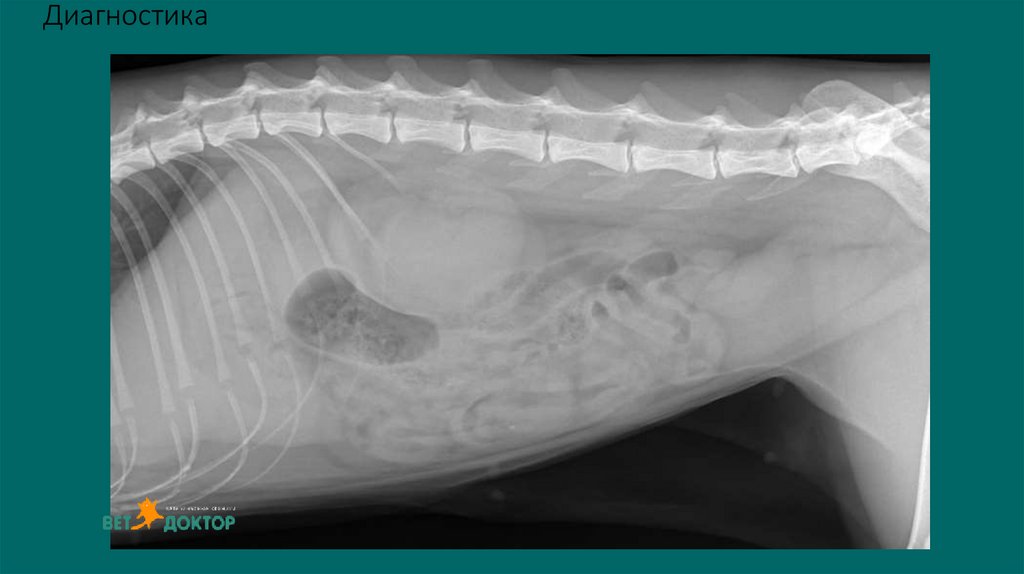

8. Диагностика

6. Рентгенологические исследования

Размер и симметричность почек, размер и топографию мочевого пузыря, размер и

положение репродуктивных органов.

У собак почки имеют бобовидную форму. Размер в 2,5-3,5 раза превышают длину L 2

У кошек овальная до круглой. Размер почек измеряют на ВД проекции в 2,4-3,0 раза

превышают длину L2

Размер проксимального отдела мочеточника :

Собаки 2-3мм. Кошки 1-2мм

Метод выявления рентгеноконтрастных уролитов (фосфат кальция, оксалат кальция,

струвиты)

Ураты /цистеиновые уролиты рентгенопрозрачны.